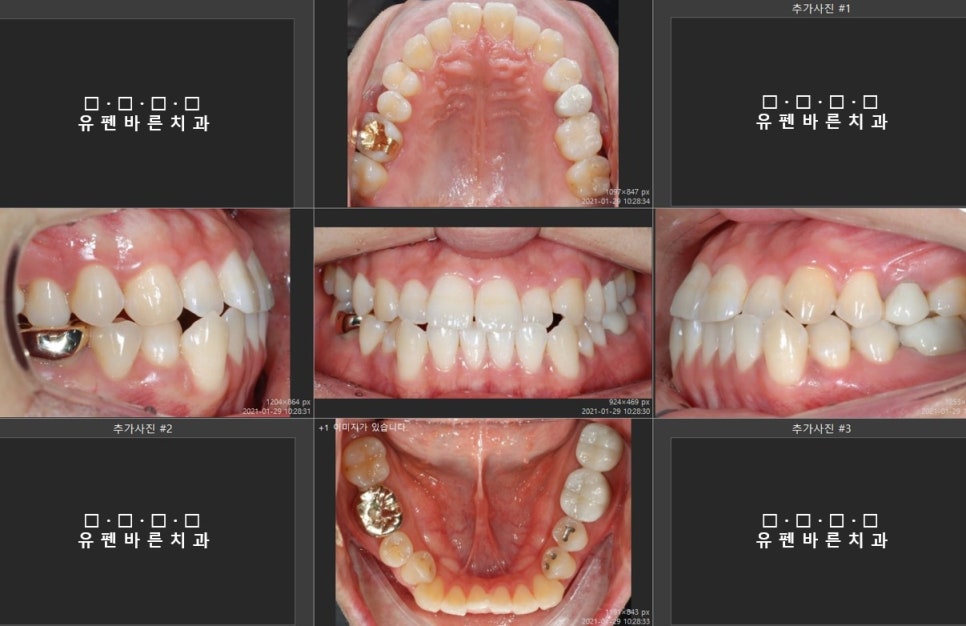

인비절라인을 시작하기전에

초진사진을 찍어보았어요

남편의 치열 상태는

윗니, 아랫니가 반대로 물리는

주걱턱 경향의 3급 부정교합 입니다.

그리고 보시다시피 상하 치아 정중앙선도

틀어져 있습니다. ㅠㅠ

부정교합이 있는줄은 알았지만

어금니 쪽을 보니

생각보다 공사가 크겠구나,,,

OMG..

원장님께 이런부정교합도 인비절라인교정으로

가능한지 여쭤보니,

원장님왈,

NO PROBLEM!